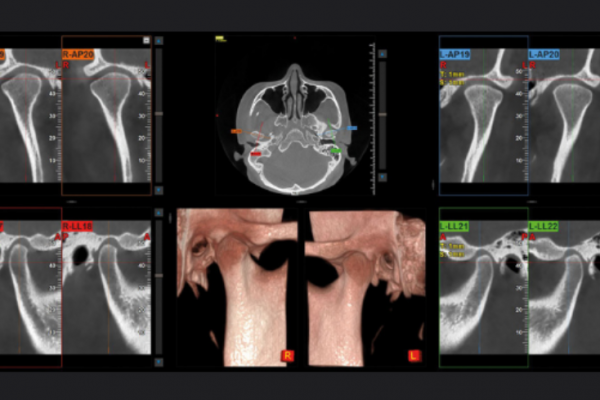

CBCT Cráneo Completo

Newton Giano

Sistema CBCT Newton Giano, líder en el sector de la radiología dental. Esta tecnología de  nos permite realizar diagnósticos detallados y precisos gracias a su capacidad para obtener imágenes tridimensionales de alta calidad del cráneo completo. Esto es fundamental no solo para la planificación y ejecución de tratamientos de implantología dental, sino también para la evaluación integral de la salud oral y general de nuestros pacientes.

Evaluación de la articulación y la mordida

Evaluar la articulación temporomandibular es esencial para garantizar la funcionalidad adecuada y evitar problemas.

Diagnóstico Vía aérea y otras patologías

El diagnóstico de la vía aérea y estructuras relacionadas es crucial para mejorar la calidad de vida.